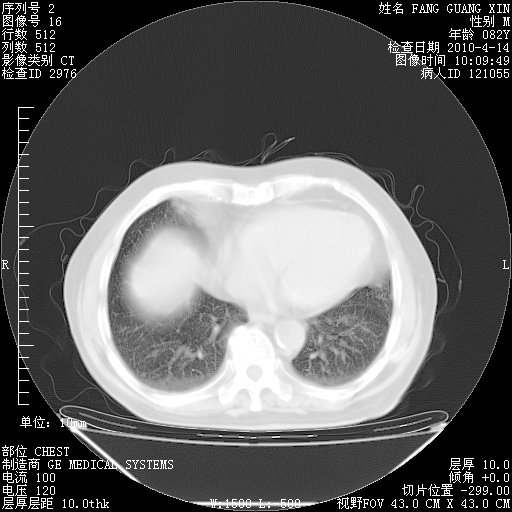

4月14日肺部CT